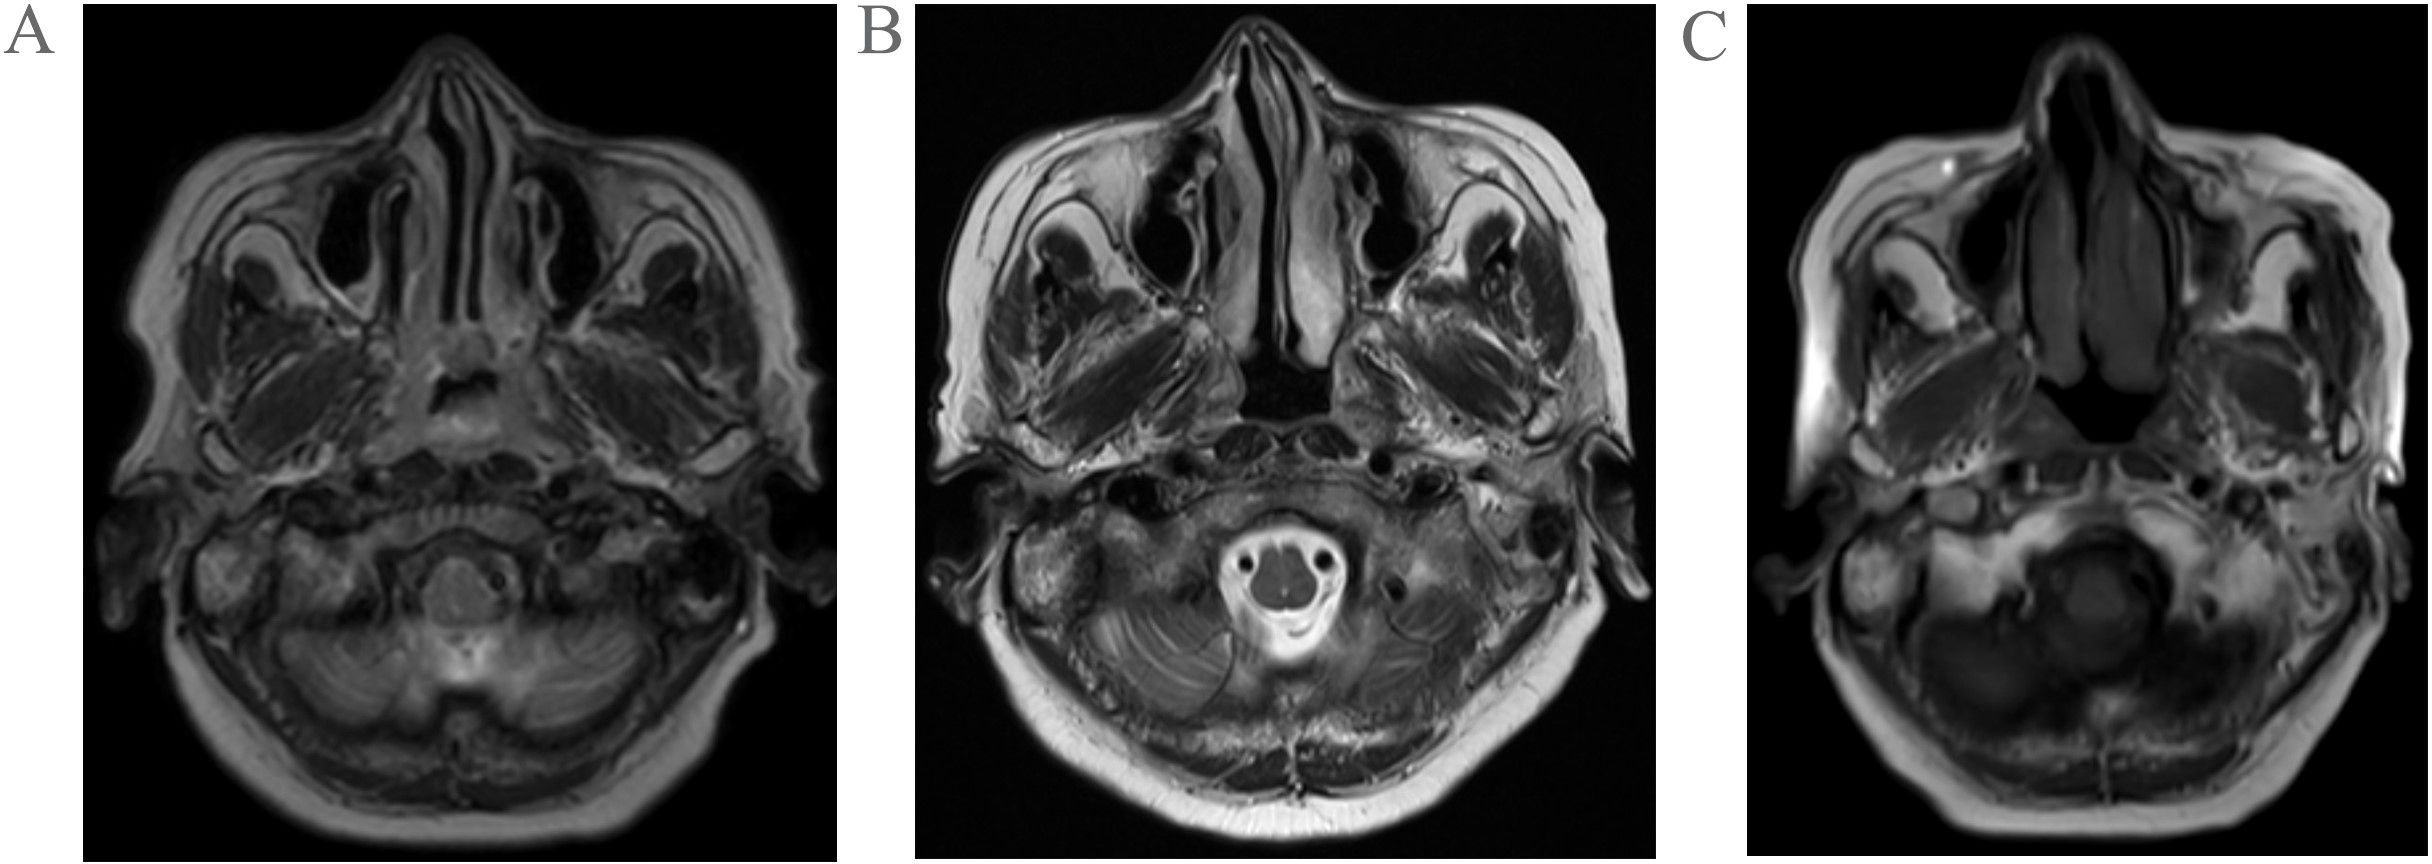

A 68-year-old woman was admitted to the hospital following the incidental discovery of a right cervical mass with a 1-day history. The patient denies any past medical history of diseases, surgeries, or allergies. Physical examination revealed multiple enlarged lymph nodes in the right cervical region. The largest lesion, located in level II, measured approximately 4.0cm×2.0cm, demonstrating firm consistency, non-tenderness, ill-defined borders, and partial mobility. No significant masses were palpated in other regions. Color Doppler ultrasound of the thyroid gland revealed multiple solid nodules in both lobes. The dominant nodule in the left lobe measured 0.3 cm×0.3 cm×0.2 cm, while the largest in the right lobe measured 0.4 cm×0.3 cm×0.6 cm. All nodules were classified as TI-RADS category III. Enlarged lymph nodes were observed in the right cervical level II and Va regions, demonstrating loss of hilar structure (suggestive of metastatic involvement). Quantitative EBV DNA testing revealed an elevated viral load of 1.28×10³ copies/mL (reference range: <4.00×10²copies/mL), suggestive of active viral replication. Magnetic resonance imaging (MRI) demonstrated marked thickening of the bilateral nasopharyngeal walls and posterior-superior walls, with multiple enlarged lymph nodes in bilateral cervical level II regions (upper jugular chain), radiologically suggestive of metastatic involvement(Figure 1A). Following comprehensive preoperative evaluation, the patient underwent concurrent ultrasound-guided core needle biopsy of cervical lymph nodes and endoscopic nasopharyngeal mass biopsy.

Figure 1. Pretreatment MRI findings of the patient (A); Post-2-cycle chemotherapy MRI findings of the patient (B); Post-1-cycle radiotherapy combined with nimotuzumab targeted therapy MRI findings of the patient (C).

The patient received two cycles of etoposide-cisplatin induction chemotherapy. Follow-up MRI performed at one month post-chemotherapy demonstrated significant regression in both the nasopharyngeal tumor dimensions and initially enlarged lymph nodes compared to pretreatment baseline measurements(Figure 1B). Subsequently, the patient underwent one cycle of targeted therapy with nimotuzumab combined with definitive radiotherapy(IMRT) to the nasopharynx and cervical lymph nodes (prescribed doses: primary nasopharyngeal lesion: total dose of 69.96 Gy in 33 fractions; cervical lymph nodes: total dose of 66 Gy in 33 fractions; subclinical disease region of nasopharynx: total dose of 59.4 Gy in 33 fractions;bilateral cervical lymphatic drainage areas: total dose of 54.12 Gy in 33 fractions). Follow-up MRI at 1 month post-radiotherapy demonstrated minimal regression of the primary nasopharyngeal tumor and persistent lymphadenopathy in baseline-involved nodal regions (Figure 1C). The patient remains on active anti-tumor therapy with ongoing clinical surveillance pending further longitudinal follow-up assessments.